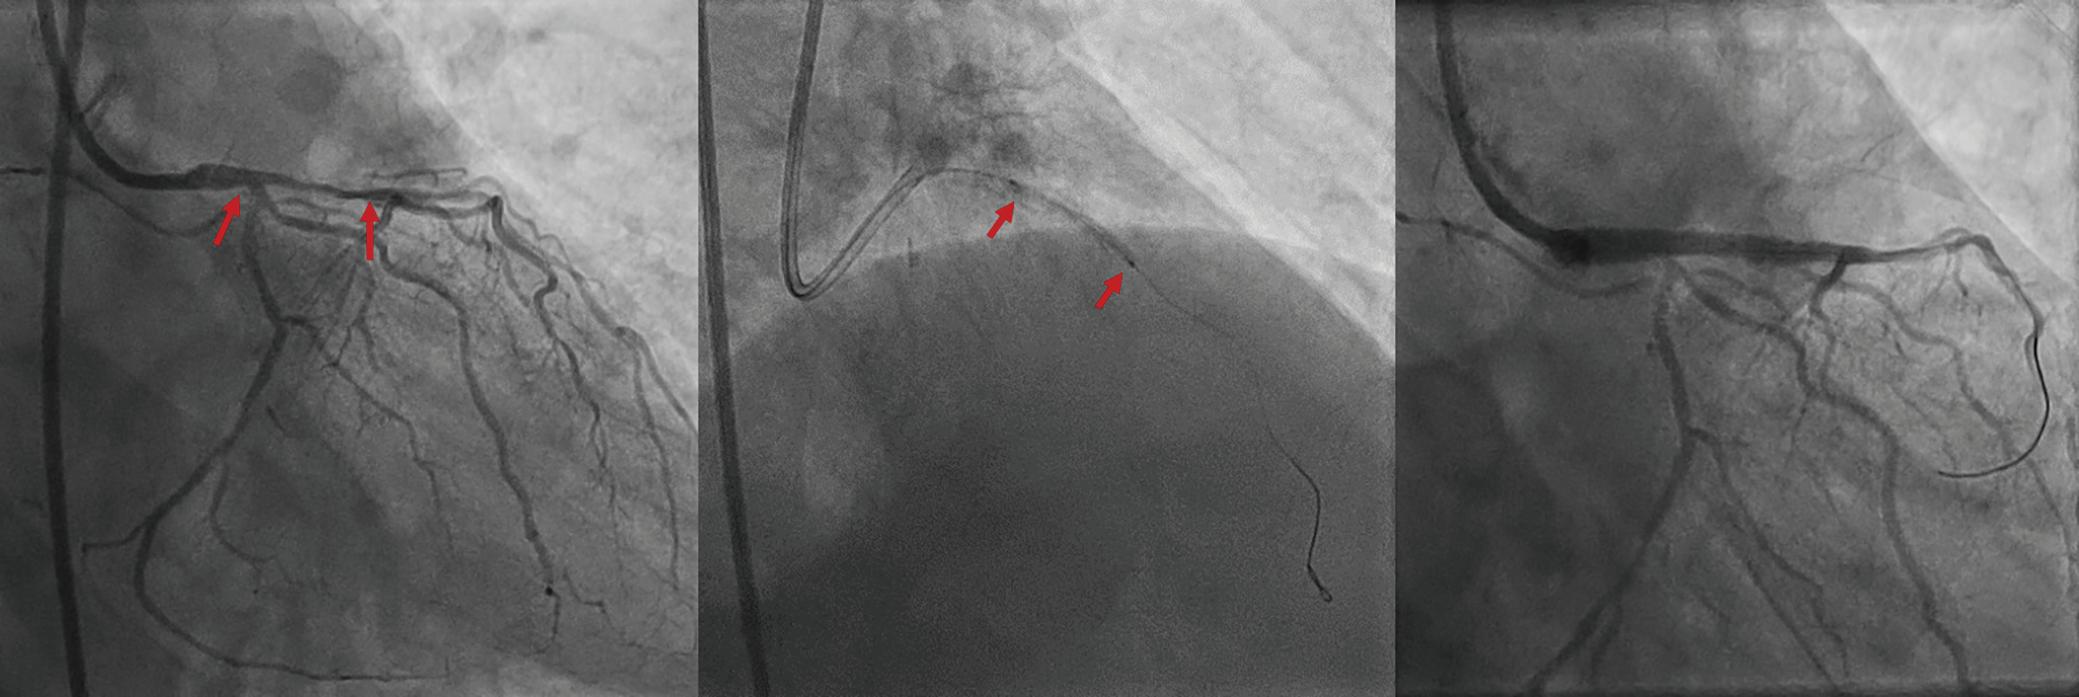

A 57-year-old man presented with a three-decade history of recurrent episodes of palpitation with alarming jugular venous pulsation, but without syncope. Each episode spontaneously reverted to the normal sinus rhythm 6–8 hours after the onset. Cardiac auscultation raised the suspicion of underlying rheumatic mitral stenosis. A 12-lead ECG was suggestive of a WPW pattern with a right posterior septal accessory pathway (Figure 1A). A chest X-ray in the posterior–anterior view was consistent with cardiac auscultation (Figure 1B). A transoesophageal echocardiogram confirmed rheumatic mitral stenosis (Figure 2A and Supplementary Material Video 1). The pliable mitral valve area was 0.8 cm2 and the mean gradient was 17 mmHg at a heart rate of 87 BPM. The coronary angiogram was normal.

On the day of the procedure, the first balloon mitral valvotomy was performed from a right femoral approach using a 23–26 mm Accura balloon (Vascular Concepts) after transeptal access using an 8 Fr SL-1 sheath and a BRK-0 needle (St Jude Medical). A transeptal puncture was performed after proper needle tip position was confirmed by fluoroscopy (right anterior oblique, left anterior oblique and 90° lateral views) and transoesophageal echocardiography (bicaval and short axis views; Figure 3A). The mean left atrial pressure prior to the valvotomy was 31 mmHg. The balloon was inflated to 26 mm in the right anterior oblique 20° position under fluoroscopy (Figure 3B) because the patient was 160 cm tall. The mitral valve area increased to 2.2 cm2 without any additional mitral regurgitation, and the mean left atrial pressure decreased to 12 mmHg without any mitral valve gradient. Immediate transthoracic echocardiography showed that the mitral valve gradient had decreased to 7/2 mmHg with negligible mitral regurgitation.

electrophysiological study and for possible radiofrequency ablation (Figure 3C). The electrophysiologist proceeded with the ablation plan.

Because the patient had baseline pre-excitation through the right posterior septal path and atrial flutter with orthodromic conduction with right bundle branch aberration, one decapolar catheter in the coronary sinus and a quadripolar catheter in the right ventricle were used to study the effective refractory period (ERP) of the accessory pathway rather than using the routine four electrophysiology catheters (three quadripolar [high right atrial, His bundle, right ventricle apex] and one decapolar catheter in the coronary sinus; Figure 4C). The supra-His conduction time was 65 ms and the infra-His conduction time was 9 ms. The baseline ECG was suggestive of a right posterior septal pathway. Right ventricular pacing showed eccentric conduction up to 450 ms, which suggested a retrograde pathway ERP of 450 ms. On pacing the integrated pathway, the ERP was found to be 450 ms. Due to the weak nature of the accessory pathway, ablation was not performed. On rapid atrial pacing, atrial flutter with right bundle branch aberrancy was induced, similar to the clinical tachycardia observed earlier. Ablation for the atrial flutter was not performed, and the patient was maintained on metoprolol succinate and an oral anticoagulant

Figure 1: ECG and Chest X-Ray

Report confirmed by I II IR aVR V1 V2 V3 V4 V5 V5 aVL aVP A B A: A 12-lead ECG showing the Wolff–Parkinson–White pattern with a possible right posterior septal accessory pathway because the R/S ratio is <0.5 in V1 and V2 and <1 in the inferior leads. B: Chest X-ray in the posterior–anterior view showing mitralisation of the left heart border, double atrial shadow on the right

side and a horizontal left bronchus. A: There was significant mitral stenosis and the mean mitral valve gradient of 16 mmHg prior to the balloon mitral valvotomy. B: Atrial flutter with 2:1 atrioventricular block and right bundle branch aberrancy was evident during the electrophysiological study by pacing the atria with a decapolar catheter in the coronary sinus at cycle length of 200 ms.

Figure 4: Electrophysiology Study to Map the Accessory Pathway

Figure 3: Transsepetal Puncture for Balloon Mitral Valvotomy and Electrophysiology Study in One Go A: Septal puncture using fluoroscopy and transesophageal echocardiography guidance. B: A 23–26 mm Accura balloon was inflated to 26 mm in the right anterior oblique view. Electrophysiological study using one quadripolar catheter for right ventricle pacing and one decapolar catheter in the coronary sinus.